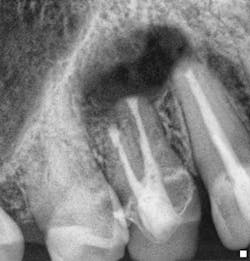

Fig. 6: Surgical preop radiograph.Endodontic treatment was necessary due to the presence of periapical pathology and acute symptoms, despite the radiographic appearance of the existing endodontic treatment being technically satisfactory. The presence of a long post, which is possibly serrated in nature and potentially actively engaging the root structure, is likely to compromise the potential for post removal and increase the risk of root fracture initiation, which would jeopardize the long-term survival of the tooth.

Fig. 7: Surgical postop radiograph.Surgical endodontic treatment was performed and the apical 3 mm to 4 mm of the root was reprepared using ultrasonics and sealed with MTA. A bone graft and resorbable membrane were placed to maximize the potential for osseous and soft tissue healing, especially with the proximity of the maxillary sinus to the surgical site. Case 2